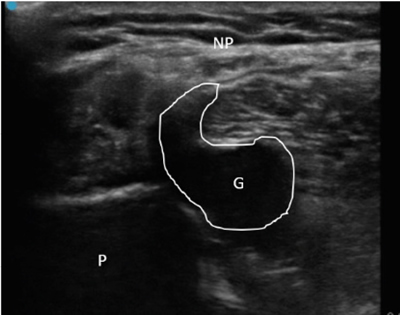

Se diagnosticó, por lo tanto, paresia de nervio peroneo derecho secundario a compresión por ganglión de articulación tibio-peronea proximal y se propuso al paciente un manejo intervencionista del mismo, que aceptó. Se realizó drenaje ecoguiado empleando una sonda lineal de alta frecuencia (10-5 MHz), una aguja de 20 G y una jeringa roscada de 5 ml (Figura 2), retirándose sin dificultad 1,5-2 ml de contenido mucinoso compatible con ganglión. Posteriormente se realizó infiltración de 1 ml de triamcinolona 40 mg ml diluida en 0,5 ml de mepivacaína al 2 %. Tras el procedimiento se evidencia una clara disminución del tamaño del ganglión.

Fig. 2. Ecografía en corte longitudinal de aspiración con aguja ecoguiada del ganglión. G: ganglión. A: aguja en interior de ganglión iniciando aspirado.